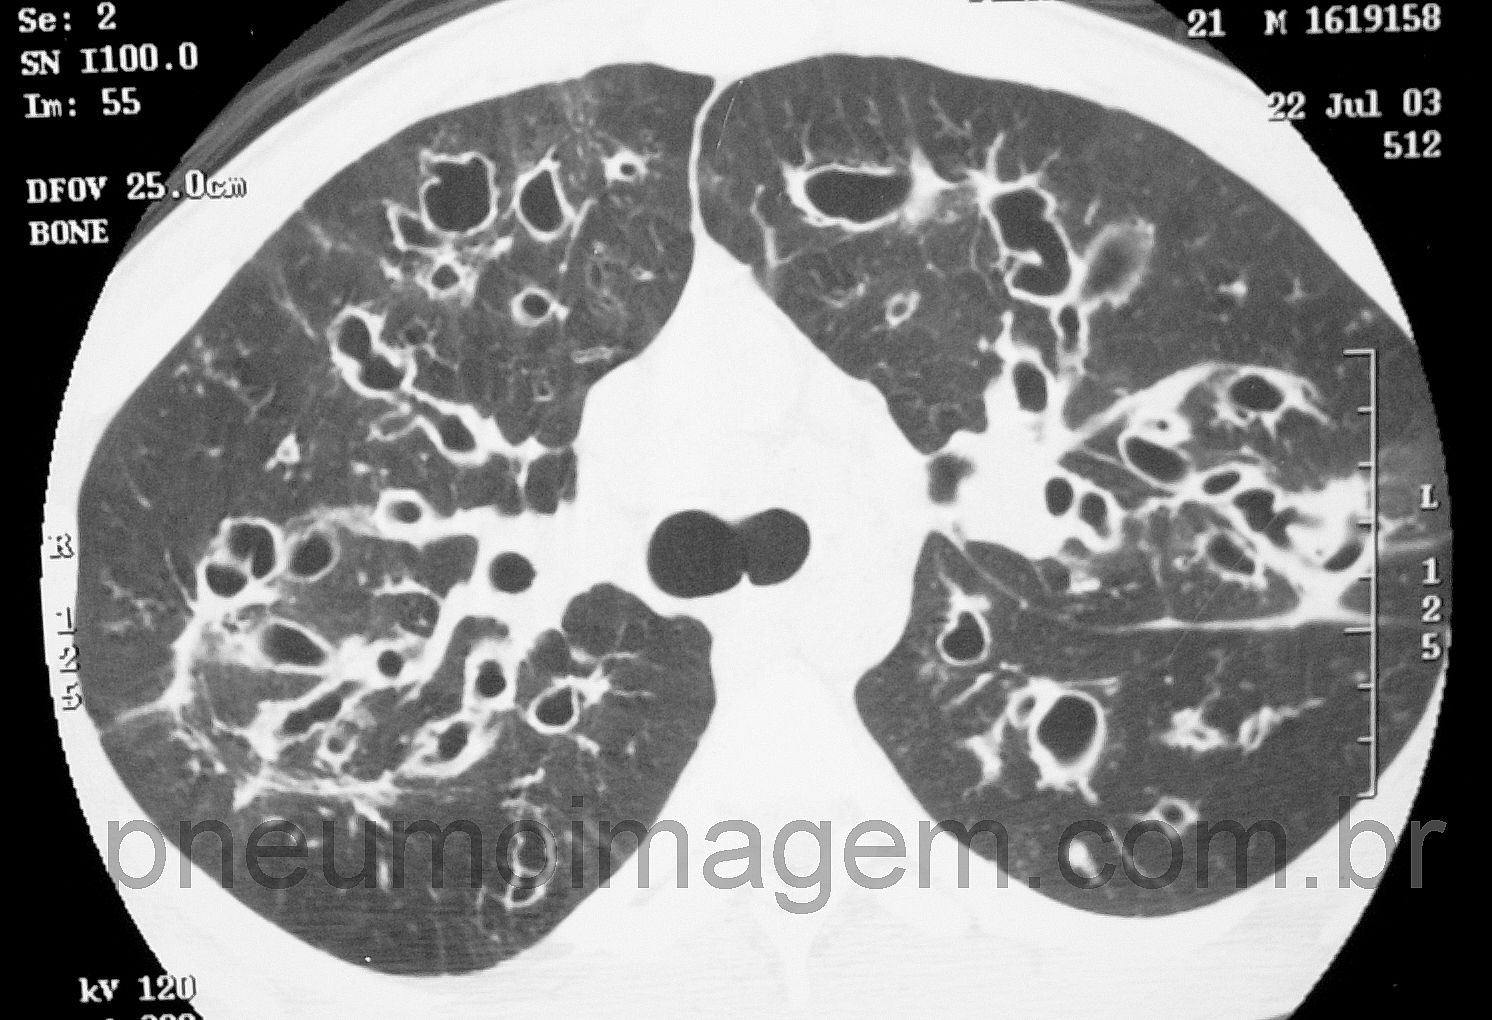

Para ver imagens de bronquiectasias por FC no PneumoImagem, clique aqui.